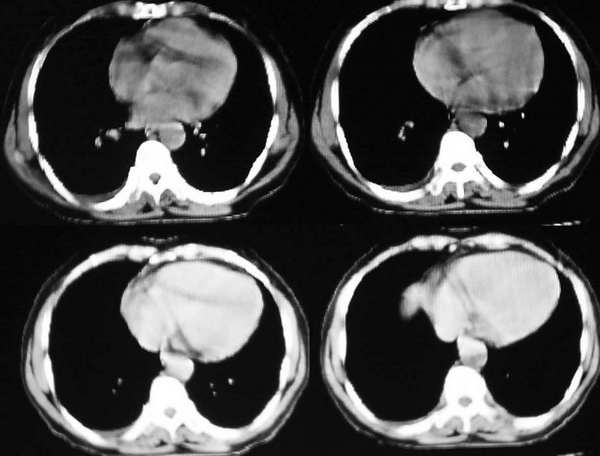

右上叶后段见大片状实变阴影,见含气支气管征,近肺门见支气管血管束增粗,上腔静脉后见小淋巴结. 后胸膜腔见少量积液. 印象:1,大叶性肺炎.2,节段性肺炎<混合菌感染>.3.建议抗炎后复查待除外其他病变

大叶性肺炎,右侧少量反应性胸水

右肺上叶肺实变,内见①支气管气像②边缘模糊③叶间裂稍饱满这些都是支持肺炎的证据。尤其是边缘模糊,其病理学依据是炎症渗出性物质通过肺泡间孔和/或呼吸性细支气管向临近的肺组织蔓延渗透,和其他表现在一起成为诊断肺炎的重要表现。